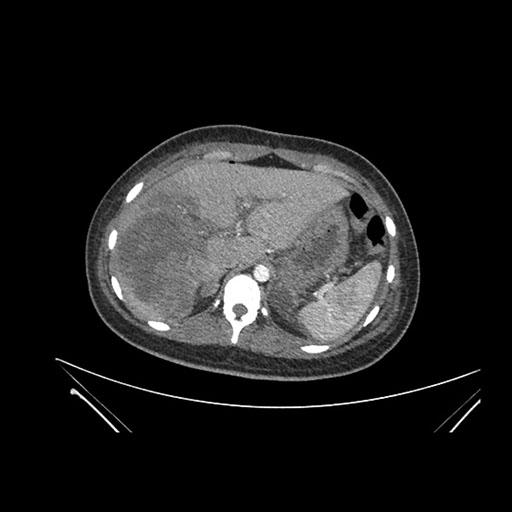

Axial Venous